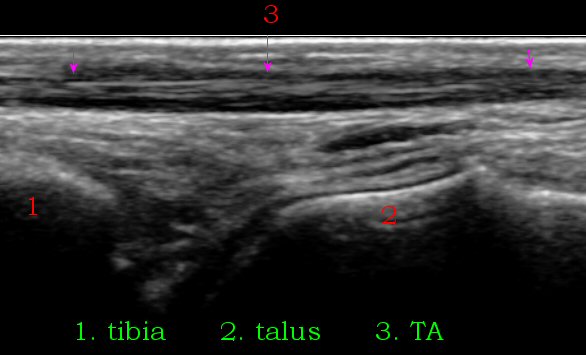

ÃÊÀ½ÆÄ À¯µµÇÏ Áֻ縦 À§Çؼ´Â ¸ÕÀú ¹ß¸ñÀÇ È¾´Ü¸é°Ë»ç¸¦ ½ÃÇàÇÏ¿© ¹ßµî µ¿¸Æ°ú ½ÉºÎºñ°ñ½Å°æÀÇ À§Ä¡¸¦ ÆÄ¾ÇÇÑ´Ù. ¹ßµîµ¿¸ÆÀº ´ë°³ À幫Áö½ÅÀü°Ç°ú ÀåÁ·½ÅÀü°Ç »çÀÌ¿¡ À§Ä¡ÇÏ°í ½ÉºÎºñ°ñ½Å°æÀº ¹ßµîµ¿¸ÆÀÇ ³»Ãø ¶Ç´Â À§Ä¡¿¡ µû¶ó ¿ÜÃø¿¡ À§Ä¡ÇÑ´Ù(»çÁø 1). ¹ßµîµ¿¸ÆÀÌ À幫Áö½ÅÀü°Ç°ú ÀåÁ·½ÅÀü°Ç »çÀÌ¿¡ Á¸ÀçÇÏ´Â °ÍÀ» È®ÀÎ ÈÄ Àü°æ°ñ°Ç¿¡ À§Ä¡½Ã۸é Àü°æ°ñ°ÇÀ» âÀ¸·Î ¹ß¸ñ°üÀý°À» È®ÀÎÇÒ ¼ö ÀÖ´Ù(»çÁø 2). Àü°æ°ñ°Ç ³»Ãø¿¡¼ Áֻ縦 ¿øÇϸé ŽÃËÀÚ¸¦ ¾à°£ ³»ÃøÀ¸·Î ±â¿ïÀÌ¸é ³»ÃøÀÇ ¹ß¸ñ°üÀýÀ» °üÂûÇÒ ¼ö ÀÖ´Ù (»çÁø 3).